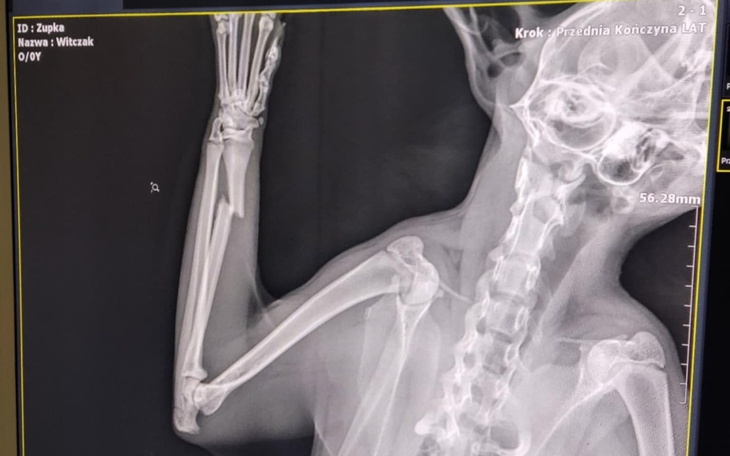

Pierwszego stycznia kotka wróciła do domu z poważnym urazem łapki. Była wystraszona i kulejąca, a my nie wiemy, co dokładnie się wydarzyło. Weterynarz podejrzewa, że mogła zostać ugryziona przez innego kota. Po kilku dniach okazało się, że łapka jest złamana, a kotka potrzebuje pilnej operacji.